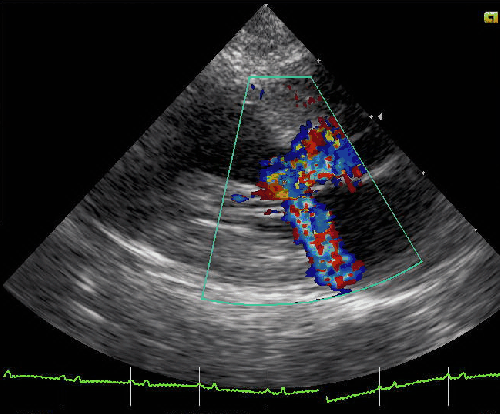

In HOCM , which is the most stressed area ? LVOT ? Septum, ? When we say stress , it can mean either mechanical or electrical .

* We know RVOT is developmentally arrhythmia prone zone . We also know HCM involves RVOT (After all , IVS is legally shared by both ventricles ! ) . Some of the monomorphic VTs with LBBB morphology may originate from RVOT in HCM .